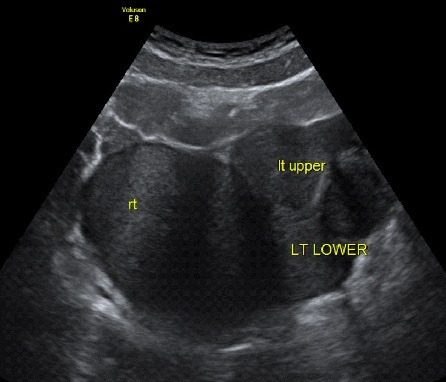

임신을 준비하는 여성들의 초음파 검사에서 관찰되는 영상입니다.

3. 자궁내막증 (Endometriosis)으로 인한 다수의 자궁내막종 (multiple endometrioma)

자궁근종이 있는지, 자궁 용종이 있는지, 난소에 혹이 있는지 확인할 수 있는 간편하면서도 정확도가 높은 검사입니다. 비용은 병원마다 천차만별이오니 꼭 미리 확인하고 가시기 바랍니다. 자궁근종, 자궁 용종, 난소에 자궁내막종의 여부에 따라 난임에 대한 접근방법이 바뀔 수 있어 필수적으로 시행하는 검사입니다.